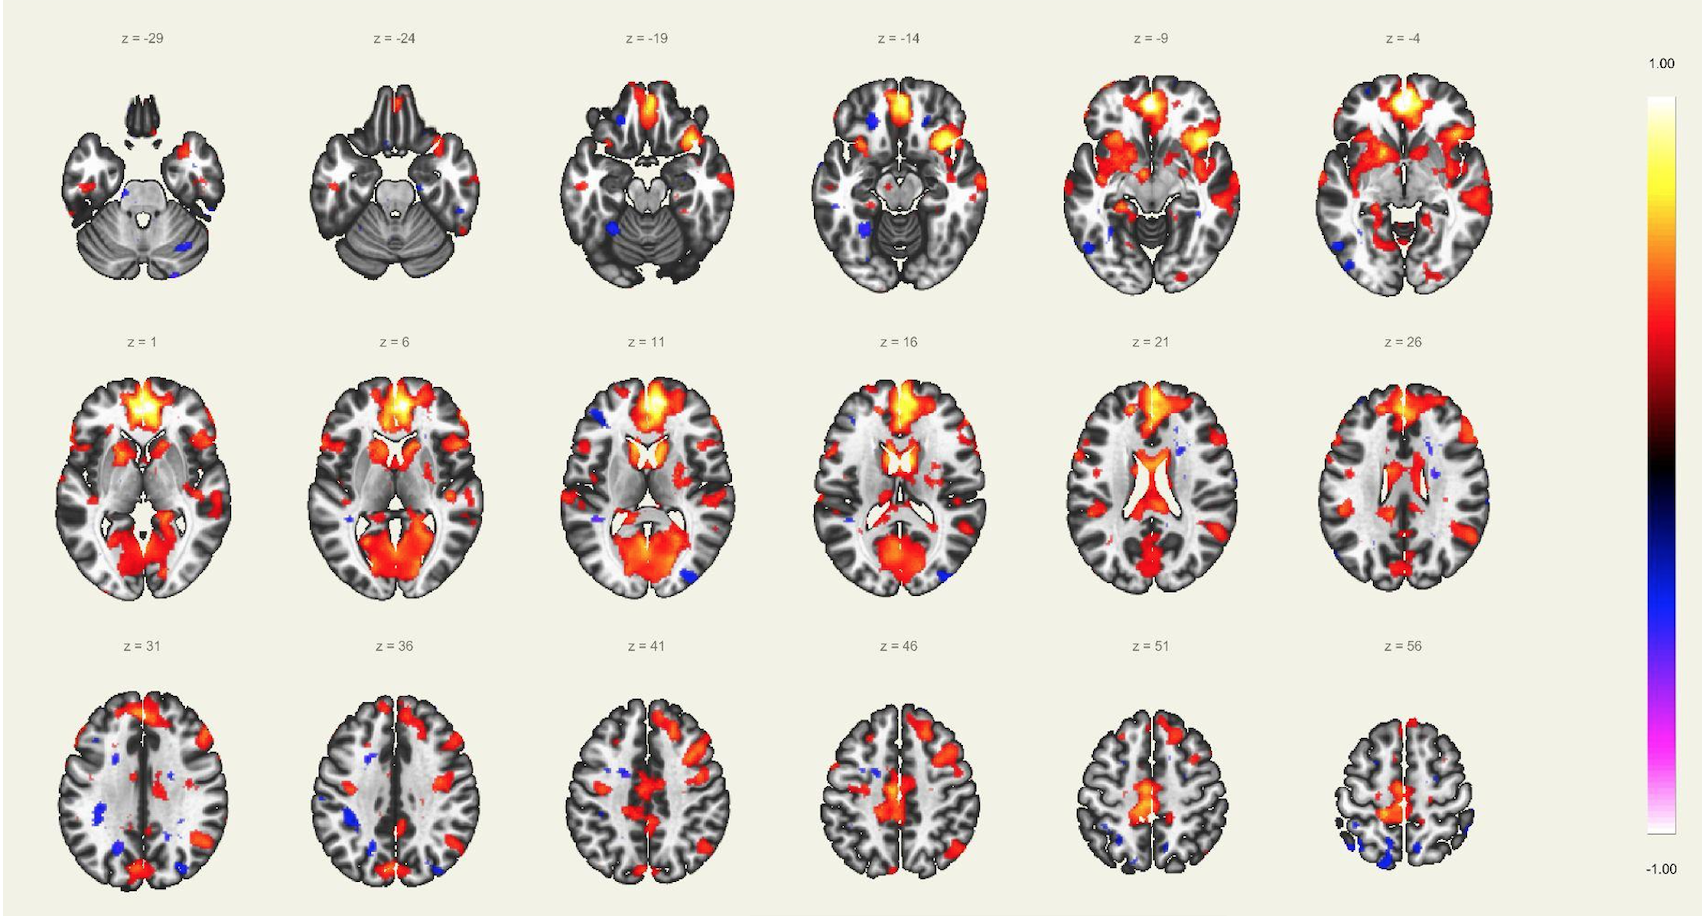

En este estudio, el escaneo se realizó con un resonador de 3 Tesla del servicio de diagnóstico por imágenes de la Clínica Internacional, a un paciente joven, sin comorbilidades ni antecedentes de importancia, el cual estuvo despierto en todo momento y con los ojos cerrados. Además, se le dio instrucciones de completar palabras mentalmente sin emitir sonido alguno o hacer gestos, llegando a identificarse las distintas redes cerebrales detalladas posteriormente.

El estudio fue realizado con secuencia BOLD, con los siguientes parámetros: cortes: 40, factor de distancia: 0%, Field of View: 240 mm, grosor de corte: 4 mm, tamaño de vóxel: 3.8 x 3.8 x 4 mm, TR: 3000 ms, TE: 30 ms, Umbral: 4 y tamaño del paradigma 20.

A pesar de la ausencia actividad física, resulta imposible indicar que no se esté realizando ningún tipo de actividad mental, como recuerdos o el uso de la imaginación. La consecuencia de esto se ve reflejada en los cambios de la actividad neuronal.16 A través de este método de vóxel semilla se ha logrado identificar distintas redes de conectividad funcional descritos a continuación:

Red Ejecutiva y Red del Control Ejecutivo

La red ejecutiva es la red que se activa al realizar exámenes como la resonancia magnética funcional basada en tareas, y se encuentra compuesta por la corteza prefrontal dorsolateral y corteza parietal posterior. Mientras que la red del control ejecutivo comprende el giro frontal medio, giro frontal superior, la corteza anterior del cíngulo, giro paracingular, corteza prefrontal ventrolateral y regiones subcorticales del tálamo. Esta red se activa durante las tareas que requieren el uso de la cognición y memoria procedimental. Principalmente suele verse en caso de actividades dirigidas y durante la realización de actividades intelectuales.

Red Sensorio-Motora:

Primera red en ser estudiada usando el método de vóxel semilla, la cual muestra la alta correlación entre las regiones motoras del hemisferio izquierdo y derecho. En esta corteza sensorio-motora, las áreas de Broddman, localizadas en la región posterior al surco central, el giro precentral y la corteza auditiva primaria, forman parte de esta red, en asociación con los núcleos ventral laterales y ventral posterior del tálamo. La activación de esta red interviene directamente en la percepción de estímulos sensorio-motores, auditivos y en el planeamiento y ejecución para el movimiento de los músculos.

Red Auditiva:

Red asociada a la red sensorio motora, comprendido por la corteza auditiva primaria bilateral, giro temporal transverso, planum polare y temporale, giro temporal supero-lateral y corteza insular posterior. Las cortezas auditivas se encuentran bien definidas para como confiables para el giro temporal transverso de cada lado respectivamente.